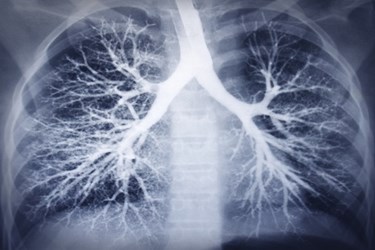

Bristol-Myers Squibb (BMS) has acquired an option to buy Galecto Biotech AB and the worldwide rights to TD139. BMS announced the move in a press release, stating that the galectin-3 inhibitor treats idiopathic pulmonary fibrosis (IPF), a type of lung disease that scars lung tissue. Galecto’s agent in Phase 1 development also shows promise in other pulmonary fibrotic conditions. BMS has agreed to pay a total of $444 million for the Swedish company and its products.

TD139 is an inhibitor of the galactoside-binding pocket of galectin-3. The agent is formulated for inhalation to target the fibrotic tissue in the lungs, without system wide exposure. TD139 inhibits the galectin-3 protein from binding to carbohydrate structures in the body, thereby limiting disease progression and scarring. Galecto develops other galectin-3 inhibitors that work to help modulate the immune system and limit pro-fibrotic activity. Galecto states that galectin-3 plays a role in many pathological processes, making it suitable for targeting in many diseases and conditions.